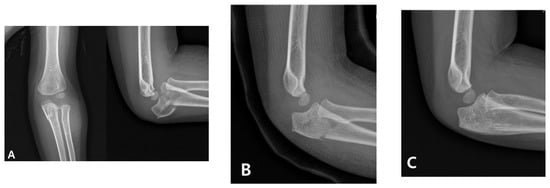

When diagnosis is delayed beyond the acute phase, the injury is considered a “neglected Monteggia fracture,” typically defined as untreated for more than two weeks. As illustrated in Figure 2, delayed treatment can result in chronic dislocation of the radial head, leading to progressive pain, valgus deformities, and a restricted range of motion [2,7]. Irreducibility due to soft tissue contracture or annular ligament entrapment may develop over time, and altered joint mechanics can result in degenerative changes and ulnar nerve dysfunction [2,8]. Surgical reconstruction (Figure 3), often involving ulnar osteotomy, open reduction, and annular ligament reconstruction, is necessary; however, the outcomes are generally inferior to those achieved with early intervention [2,9].

Figure 3. Surgical correction of a neglected Monteggia fracture-dislocation. (A) Preoperative radiographs of a 5-year-old boy showing persistent anterior dislocation of the radial head due to a previously unrecognized Monteggia lesion. (B) The patient underwent corrective ulnar osteotomy and open reduction surgery. Postoperative imaging confirmed the successful reduction and restoration of the radiocapitellar alignment.